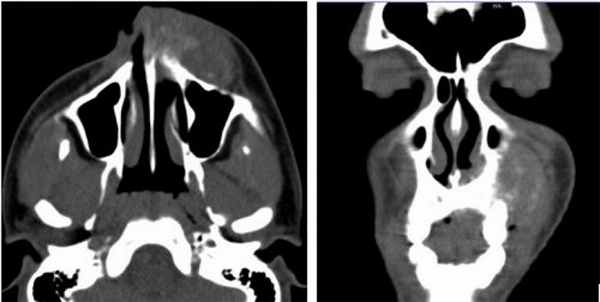

Пациент, муж, 19 лет обратился с жалобами на припухлость левой средней трети лица (Рис. 1).

Рис. 1. КТ свидетельствует об остеосаркоме, опухолевый инфильтрат происходит из передней стенки верхней челюсти слева, с вовлечением альвеолярной кости (остеолиз).

Клинический случай №2

Пациент муж., 16 лет, в анамнезе удаление зуба год назад. Обратился с жалобами на резкое увеличение объема лица слева, дисфагию и трудности при разговоре в связи с давлением опухолевой массы на глотку (Рис. 2,3).

Рис. 2. КТ свидетельствует об остеосаркоме, поражена левая половина верхней челюсти, вовлечены крыловидный отросток и нижняя челюсть с инфильтрацией в виде солнечных лучей и выраженной периостальной реакцией. Ассоциированные деформация и отек мягких тканей.

Рис. 3. 3d-реконструкция остеосаркомы с деформацией и отеком мягких тканей.